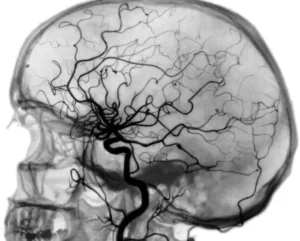

- Съемка. Рентгеновский аппарат делает серию снимков, на которых видно, как именно контрастное вещество проходит по сосудам. Специальная компьютерная программа «вычитает» (субтрагирует) все лишние структуры, такие как кости и мягкие ткани, оставляя на изображении только сосудистую сеть.